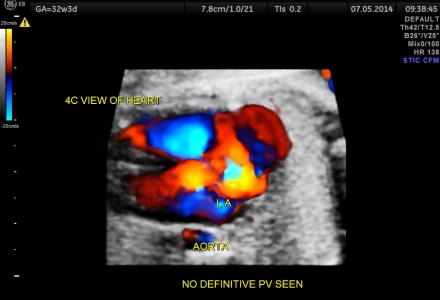

Total Anomalous Pulmonary Drainage